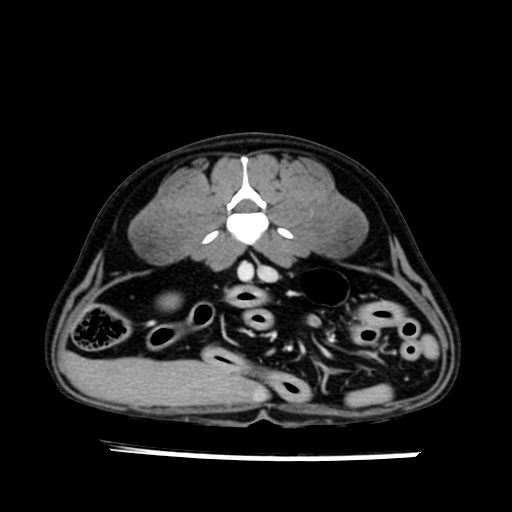

prescritto esame TAC

sequenza immagini limitata al fegato reni e surreni

le immagini ecografiche rispetto alla tac datano circa 7 mesi prima ,le surrenali sono normali nonostante il test acth sia risultato positivo .all’esame TAC dopo diversi mesi risultano aumentate armonicamente nel volume e si individua un forte sospetto di adenoma ipofisario .

sospetto adenoma ipofisario vs. meno probabilmente meningioma della base; intertiziopatia polmonare; lesione espansiva epatica, verosimilmente del lobo laterale sinistro, di sospetta natura neoplastica; lesioni spleniche di natura da definire; iperplasia/ipertrofia delle ghiandole surrenali, bilateralmente; vertebra di transizione del rachide toracico; tenosinovite cronica del muscolo bicipite brachiale di destra.